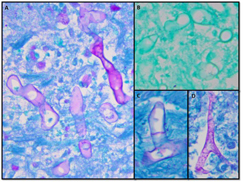

Autopsy revealed a large, complex pseudocavitary lesion formed by necrotic omentum encasing several necrotic loops of small bowel with partial entrapment of the transverse colon and two large necrotic abscess cavities in the mesentery and below the stomach. A definite perforation was not identified by gross examination. A large annular, hemorrhagic, necrotic lesion corresponded to the superficial ecchymosis on the left upper to mid quadrant abdominal skin (Fig. 2). Microscopic examination of involved tissues revealed extensive infiltration by PAS-positive, GMS-negative fungal organisms with prominent angiotropism. Some fungal forms showed Zygomycetes morphology with aseptate, ribbon-like hyphae of variable width (Fig. 3). However, some hyphae showed features not typically associated with Zygomycetes, including septa formation, narrower hyphae, and 45-degree angle branching (Fig. 3). Postmortem viral, bacterial, and fungal cultures from the omentum, brain, spleen, liver, kidney, right and left lungs, peripancreatic necrosis, and retro-gastric abscess revealed no evidence of disseminated fungal infection; however, the lungs, omentum, kidney, liver, and brain grew Enterococcus species. Extensive sampling of the tissues showed no lymphoma.

Due to ambiguous fungal morphology, PCR analysis of formalin-fixed paraffin-embedded tissue from the peripancreatic necrosis and retro-gastric abscess was performed with methods reported previously.3 PCR products were separated by electrophoresis using a one percent agarose gel. PCR using primers directed against internal transcribed spacer (ITS1) yielded a product that was subjected to bidirectional sequencing and contig assembly. Assembled sequence was submitted to GenBank Basic Local Alignment Search Tool (BLAST) search. The query sequence matched 100 percent over 312 base pairs to Rhizopus microsporus (GenBank accession No. DQ119009) and Rhizopus azygosporus (GenBank accession No. DQ119008) sequences (Fig. 4).

Diagnosing zygomycosis is difficult because tissue culture is often negative.5 Although the gold standard for diagnosis is histologic examination, fungal morphology, even aided by special stains (PAS and GMS), is unreliable5 for use as the only means of identification. There is a chance for incorrect diagnosis if adequate fungal hypha or the classic morphology is not seen. In addition, microscopy cannot differentiate fungi beyond the genera level. Fluorescent antibody staining and newer immunohistochemical methods have shown improved identification over conventional modalities (H&E and special stains); however, these methods are not yet widely used.5 Culture-independent nucleic-acid based methods such as PCR are rapid and sensitive and can be used on fresh or formalin-fixed tissue. Targeting of multi-copy loci, particularly the ribosomal DNA genes (18S, 28S, and 5.8S) and the intervening internal transcribed spacer (ITS) regions (ITS1 and ITS2), allow increased specificity with identification to the species level.6 Such specificity is important in selecting appropriate antifungal therapies.